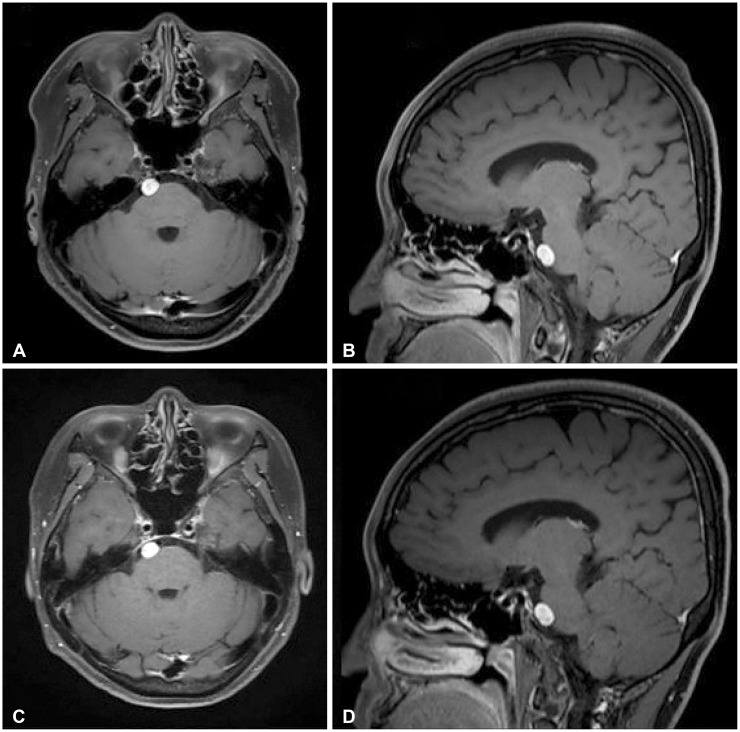

This case introduces the differential diagnosis of a well-enhancing lesion in the prepontine cistern of a 55-year-old female patient who was diagnosed with recurrent metastatic breast cancer. The patient was diagnosed with breast cancer 11 years ago and underwent a mastectomy and subsequent adjuvant therapy. Tamoxifen had been given for 5 years, and the treatment was completed. Five years after, she found a lung nodule on her routine chest X-ray examination. Based on her past medical history, systemic cancer work-up was done and it revealed multiple lesions in T10 vertebra, lungs, and mediastinal lymph nodes. Trans-bronchial needle aspiration was performed and the biopsy was a metastatic breast cancer. Brain MRI was taken as she was complaining of headache and it showed a well-defined, ovoid enhancing 0.9-cm nodule in the right prepontine cistern. Neuro-oncology tumor board evaluated the lesion as more likely to be an asymptomatic neurogenic tumor rather than metastasis based on radiological features including brainstem surfaced location, slightly high signal intensity on T2-weighted image and no diffusion restriction. To rule out leptomeningeal metastasis, a serial cerebrospinal fluid cytology examination (×3) was done and negative for malignant cells. Follow-up brain MRIs of 2 and 9 months showed no significant changes in the pre-pontine enhancing lesion.